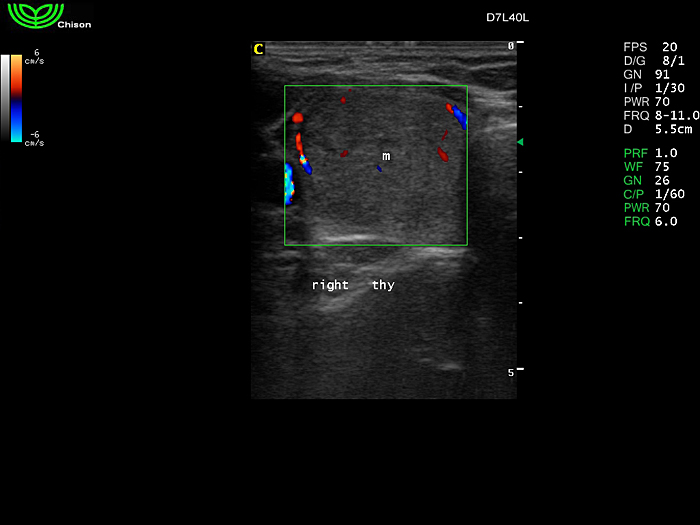

D7L40L 7.5МГц, линейный.

4.0МГц – 13.0 МГц. Применения: грудь, малые органы, нервы, сосуды, венозная катетеризация, мышцы и скелет, управление биопсией. |